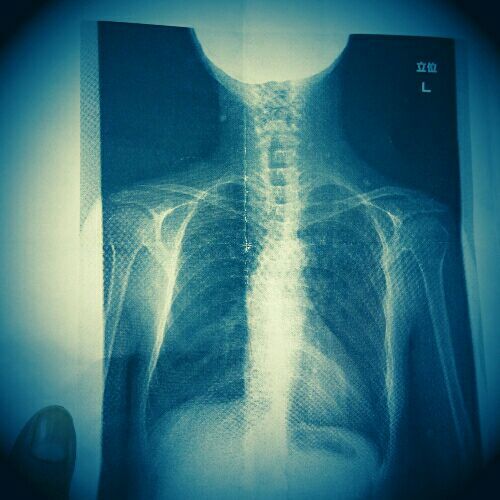

今現在は脊柱側弯症の症状。

rblog-20161016002439-00.jpg

背骨が文字↑